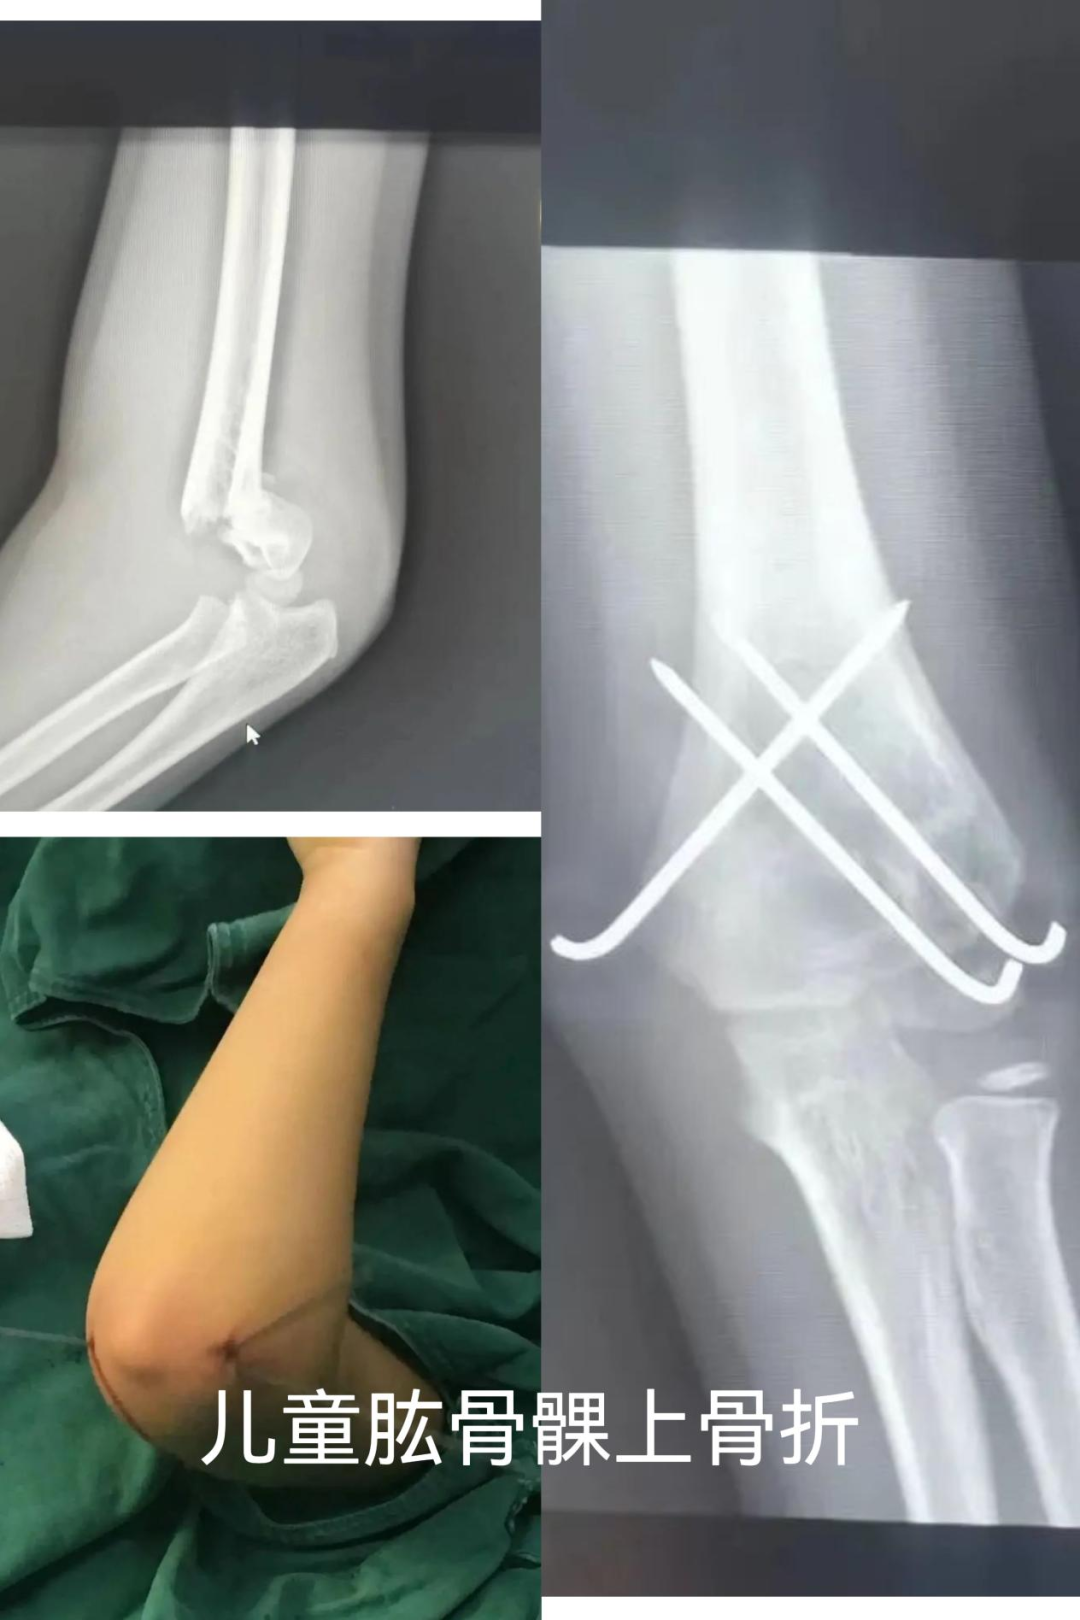

1. 年轻患者(尤其是儿童和青少年)

骨骼还在生长:对于儿童,内固定物可能影响骨骼的发育或生长板,通常需要择期取出。

局部疼痛与摩擦:常见于皮包骨头的地方,比如脚踝外侧、锁骨、肘关节。钢板紧贴皮肤,摩擦软组织或肌腱,引起疼痛、活动时弹响或局部滑囊炎。

影响关节活动:部分钢板放置位置可能轻微影响关节活动度,取出后有助于功能恢复。